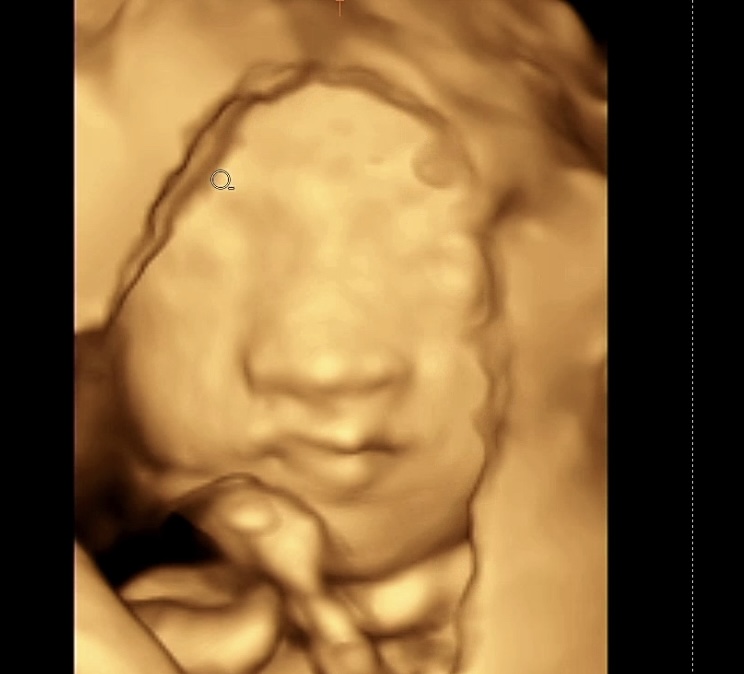

출산이 점점 임박해 오니. 출산 시기 고민이 정말 많이 되더라구요

과거 39주 출산이 일반적이었으나, 최근 39주미만 출산이 증가하면서 문제가 발생하고 있습니다.

의학적으로 39주 출산을 권장하며, 가능하면 40주까지 채우는 것이 이상적입니다.

특히 임신마지막 시기에 아기의 뇌가 급격히 성장하므로, 최소 39주를 채워 출산하는 것이 아기의 건강에 매우 중요합니다.